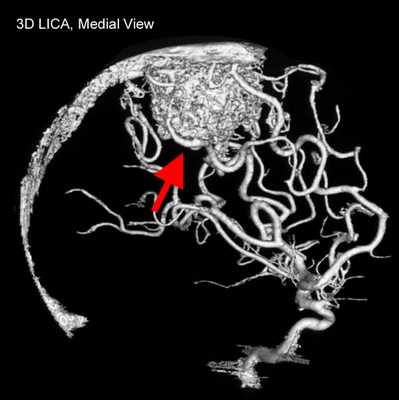

3D-модель церебральных артерий и вен

На фоне ядерного резонанса возникает слабый электромагнитный сигнал, который считывают при помощи чувствительных детекторов. Информацию обрабатывают, данные преобразуют в серию послойных снимков и транслируют на монитор компьютера.